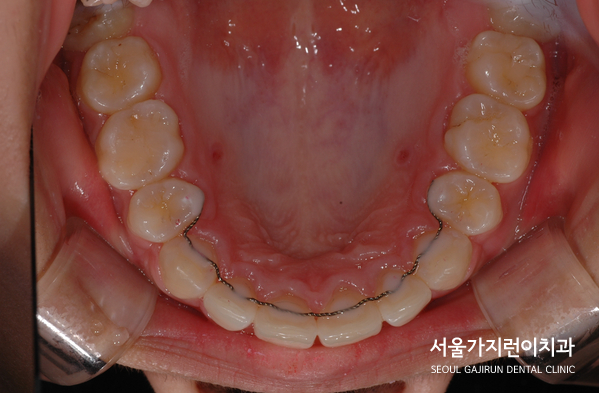

하악 역시 어금니의 교합이 정상적으로 맞춰지는 것을 확인하고 미니스크류를 식립해 진행했습니다. 이후 발치 공간을 닫아주기 위해 탄댐설측교정을 진행했는데요. 윗니는 설측교정으로 아랫니는 순측교정으로 콤비교정을 진행했는데요. 두 개의 와이어를 거는 탄댐설측교정으로 옥니를 방지해 치아교정을 진행했었습니다.

이후 사진을 보면 앞니의 뻐드러짐이 사라진 것을 확인할 수 있었는데요. 돌출입 증상과 무턱 증상 모두 개선해 안모 변화가 크게 변화된 것을 확인할 수 있었습니다.